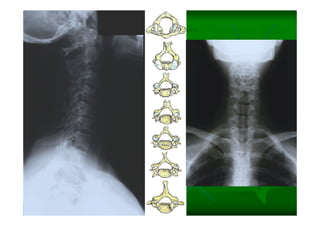

Este documento describe la columna vertebral humana. Está compuesta de 33 vértebras divididas en 7 cervicales, 12 torácicas, 5 lumbares, 5 sacras y 4 cóccigeas. Cada vértebra posee un cuerpo, pedículo, apófisis transversas, apófisis espinosa e inferior y laminas. Las curvaturas de la columna son la lordosis cervical y lumbar y la cifosis torácica y sacra.